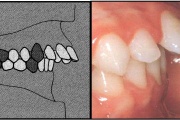

Valehambumus

Hammaste asendianomaaliad on tingitud tavaliselt arenguhäirest.